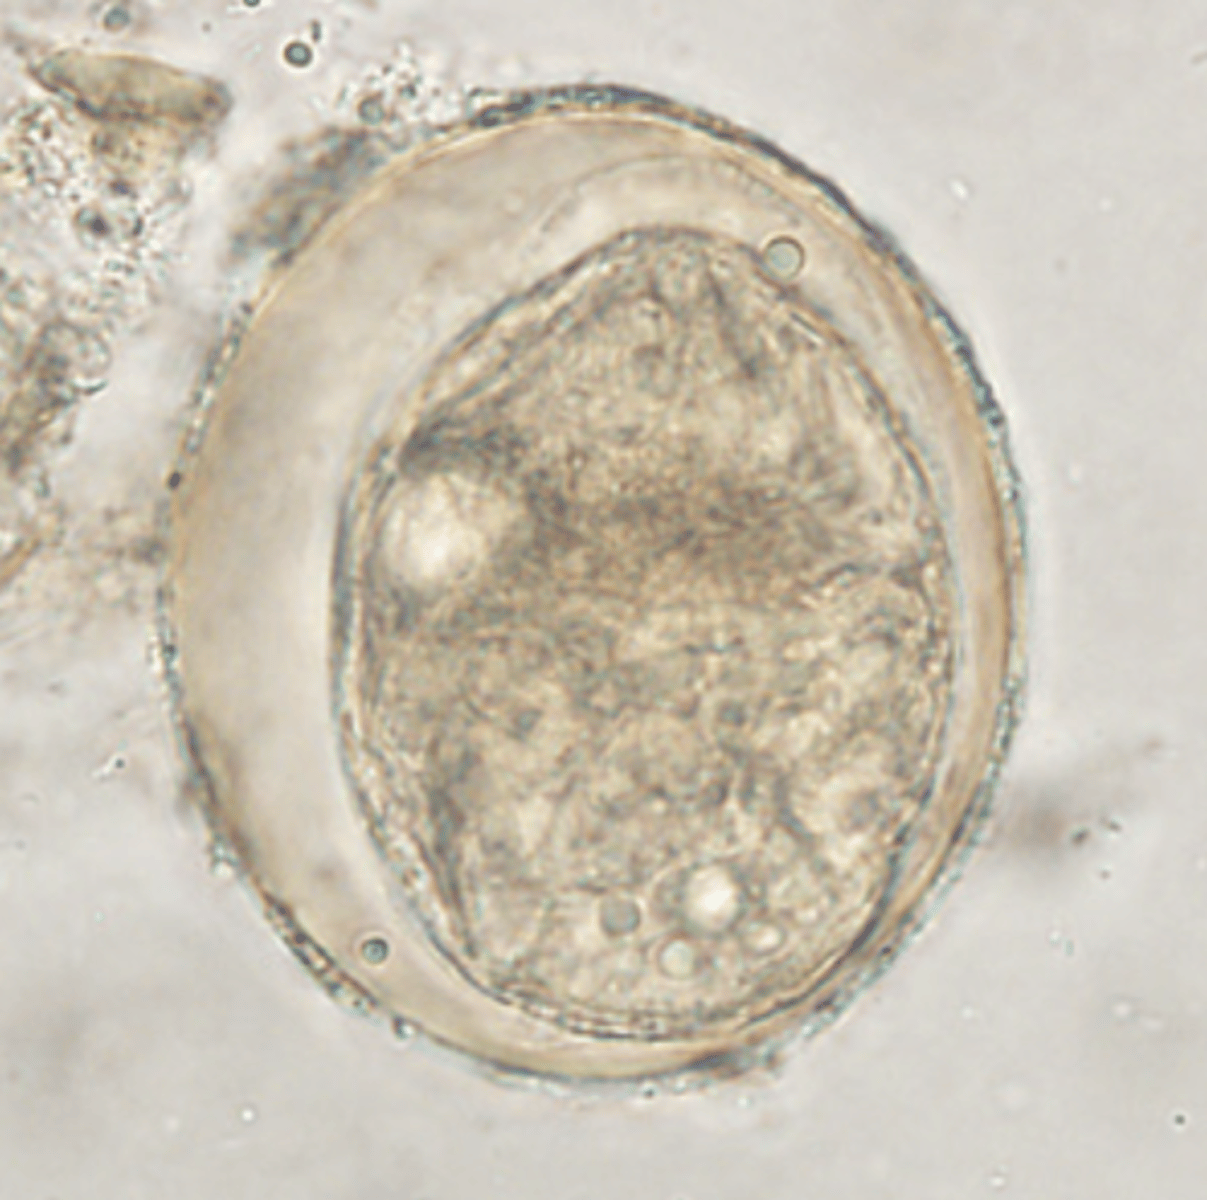

Hymenolepis nana